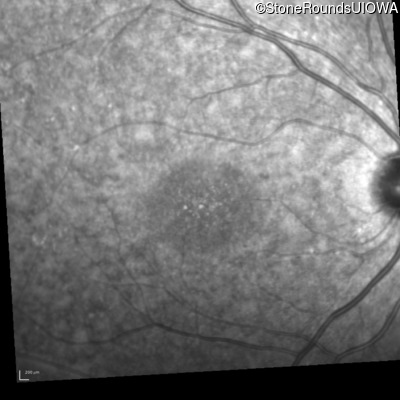

Infrared Fundus Photograph - Right - 20/25 +1 sc

Exemplar